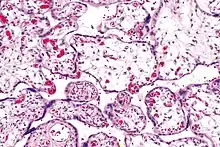

| Micrograph of villous immaturity. H&E stain. | |

Placental villous immaturity is chorionic villous development that is inappropriate for the gestational age.

Immature chorionic villi are larger and have more central blood vessels; thus, the diffusion distance for gas and nutrient exchange is larger and, therefore, placental function is impaired.